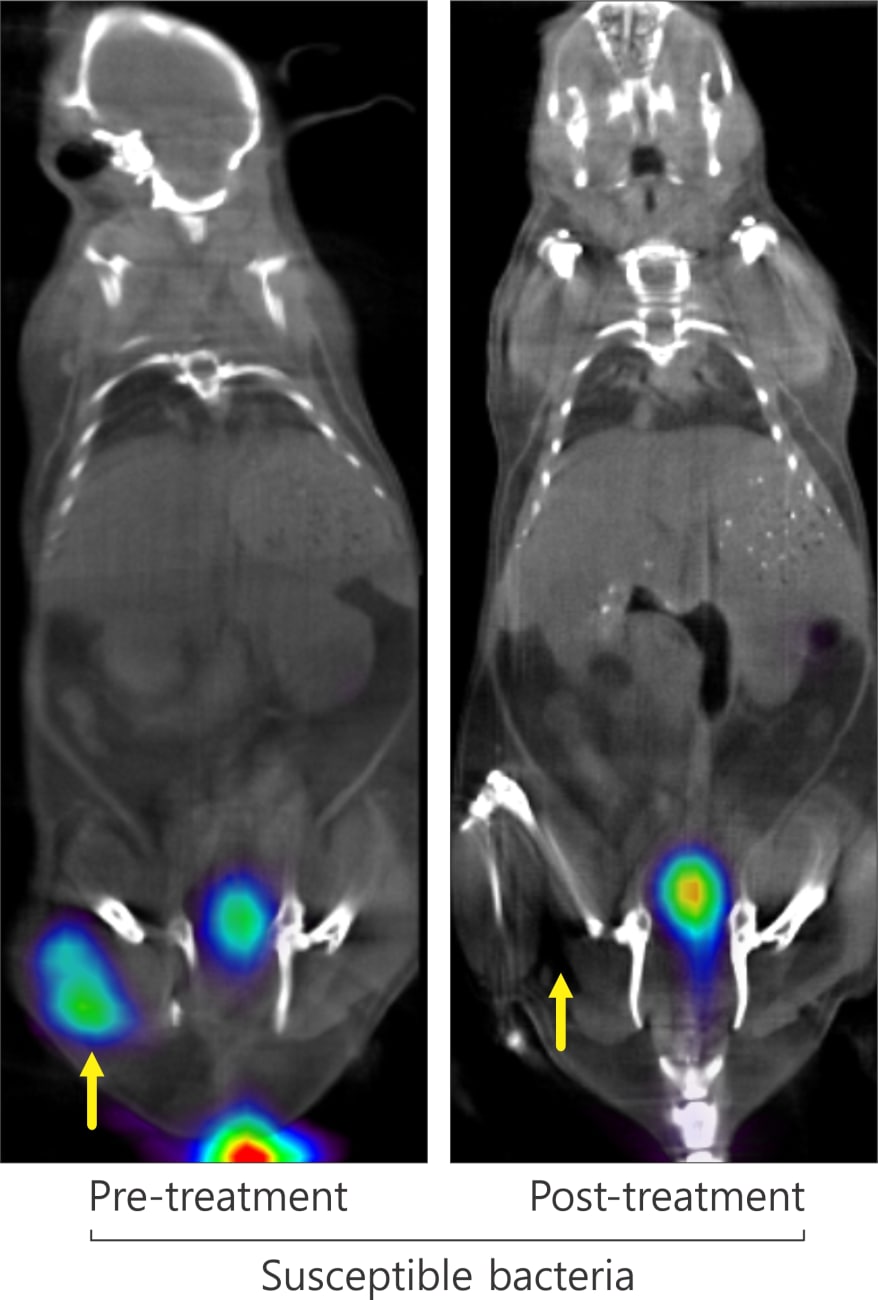

Another clinically important finding was the researchers’ ability to visualize quickly the efficacy of antibiotic treatment by comparing PET scans before and after treatment. In mice infected with drug-susceptible E. coli, the initial signal disappeared after treatment, but mice infected with multidrug-resistant E. coli showed a magnified signal, indicative of a higher bacterial burden.